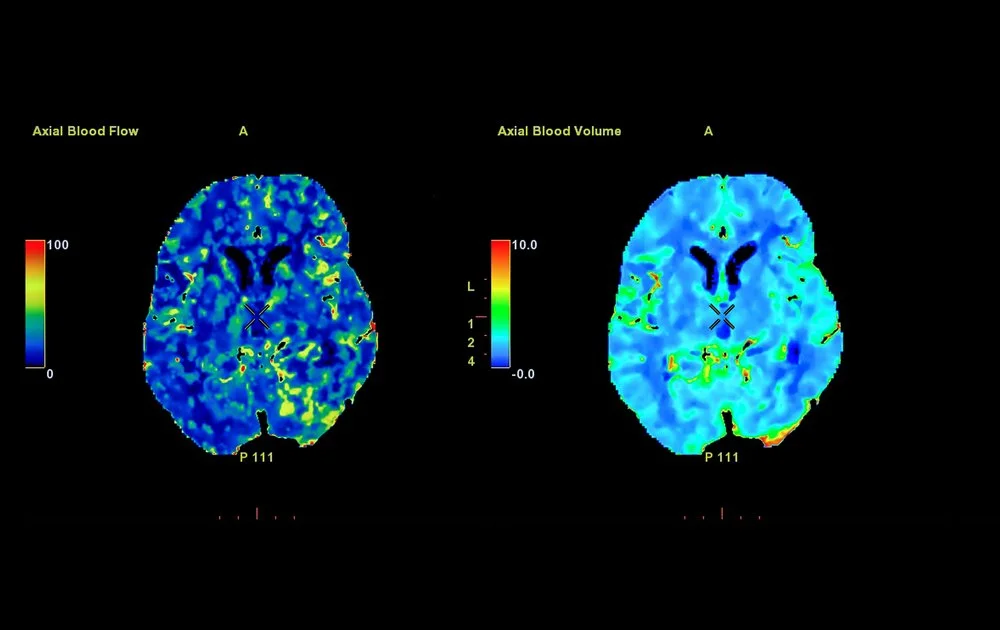

Research Review on effect of acupuncture on brain scans of people with Alzheimer's disease (AD) and mild cognitive impairment (MCI).

Alzheimers and Dementia in general, are terrible diseases. The effect on the patients and their families and care givers is immense. Loosing cognitively function or watching your loved one slip away is heart wrenching and difficult to say the least. In this paper they did a research review of 58 different studies to look at the effect acupuncture on the brain scans of people with Alzheimer's disease (AD) and mild cognitive impairment (MCI). They “employed 8 neuro-imaging techniques and 29 outcome measures, with a primary focus on brain functional activation regions and brain functional connectivity.” They found “acupuncture for AD and MCI demonstrates clear efficacy, which is supported by imaging evidence.”